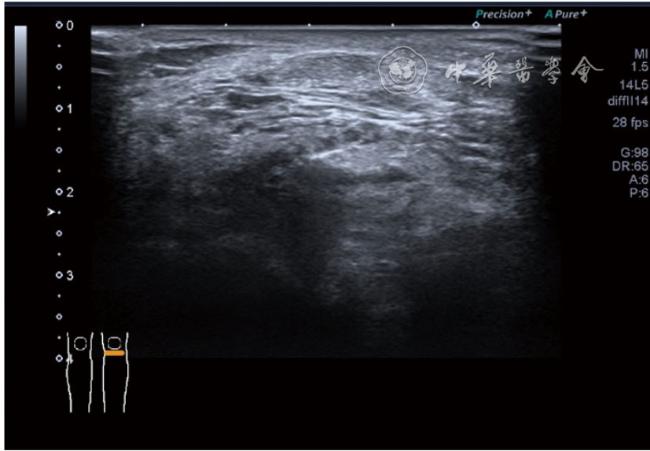

3.膝关节内局部治疗。随着病情发展,静态结构失衡,膝关节内部结构发生变化,会出现软骨损伤、脱落,关节间隙变窄,内外间隙不等,骨赘形成等。膝关节内局部治疗包括关节内症状性骨赘剥离、玻璃酸钠及PRP注射等。(1)膝关节内症状性骨赘针刀剥离松解治疗。由于软骨缺损或者力平衡失调,在关节内脱落软骨区会出现骨赘。部分骨赘引起疼痛,或者与髌骨撞击出现临床症状需要治疗。针刀剥离目的不是去除骨赘,而是剥离松解,缓解或者消除疼痛。以股骨外髁骨赘为例。患者平卧位,膝关节屈曲100°~120°。一般选用10 MHz超声探头,穿刺区域常规消毒,探头涂抹耦合剂后套入无菌手套碘伏消毒或使用无菌耦合剂。将探头置于患者皮肤表面,短轴扫查,显示关节面与骨赘,选用25G注射针,抽吸1%利多卡因3 ml于骨赘周围进行分层麻醉。选用直径1 mm的Ⅰ型2号针刀,在超声引导下从外侧向内侧到达骨赘,反复剥离,一般5~8刀后拔出针刀结束治疗(图18),局部压迫5分钟,无菌敷料覆盖。(2)膝关节髌上囊积液治疗。髌上囊积液在膝关节骨关节炎比较常见,尽管积液量可能很大,但通过软组织松解治疗后,大部分患者积液会减少或者消失。所以积液的治疗可以放在后面处理。超声引导下抽出积液,药物注射是常用的治疗方法。膝关节炎积液的治疗通常包括关节内皮质类固醇激素或者臭氧注射。如果慢性以滑膜丛型增生为主,针刀有限切割增生滑膜加药物注射可提高疗效。①髌上囊积液抽吸加臭氧注射治疗。患者平卧位,膝关节屈曲30°~60°,膝下垫一软枕。选用10 MHz超声探头,治疗前消毒准备同骨赘针刀剥离松解治疗。将探头置于患者皮肤表面,短轴扫查,找到积液最多处,应用22G针头,直接穿刺进入髌上囊抽出液体,然后根据髌上囊大小制备35 μg/L的15~20 ml臭氧注入髌上囊内拔出针头(图19),局部压迫2分钟,无菌敷料覆盖。②髌上囊慢性滑膜炎针刀切割松解治疗。患者平卧位,膝关节屈曲30°~60°,膝下垫一软枕。选用10 MHz超声探头,治疗前消毒准备同骨赘针刀剥离松解治疗。将探头置于患者皮肤表面,长轴或短轴扫查,找到积液最多处,用一次性5 ml注射器抽吸1%利多卡因3 ml于髌上囊进行分层注射麻醉,囊内也要注射适量麻药,尽量抽出积液。选用直径1 mm的Ⅰ型2号针刀,长轴扫查从近端向远端,短轴扫查从外侧向内侧,在超声引导下进入囊肿内对内壁及增生滑膜的不同方向、角度进行反复切割(图20),一般2~3分钟拔出针刀,然后囊内注射1%利多卡因3 ml+曲安奈德15 mg,结束治疗,局部压迫5分钟,无菌敷料覆盖。(3)膝关节腔PRP注射治疗。关节腔注射主要是为了修复软骨,如果不是为了治疗积液,不主张应用激素类药物。目前主要的注射药物为玻璃酸钠、PRP。按照传统的注射部位,多为髌上内、外或者髌下内、外注射点,但是超声不能观察到注射针的位置,药物也不能很好到达软骨损伤的部位,效果受到影响(图21)。膝关节软骨损伤的主要部位在髌股关节的股骨髁,超声可以很好地显示这一部位,并能显示软骨变薄。因此,由这个路径平面内进针注射,可以很好显示穿刺针的路径与位置。以注射PRP为例。患者平卧位,膝关节屈曲100°~120°,选用10 MHz超声探头,治疗前消毒准备同骨赘针刀剥离松解治疗。将探头置于患者皮肤表面,短轴扫查显示关节面,应用25G注射针头,抽吸1%利多卡因2 ml由内侧进针进行分层麻醉直达关节软骨面。制备4.5 ml PRP,直接注射到关节面,液体顺关节面分布,注射完毕拔出针头(图22)。局部压迫2分钟,无菌敷料覆盖。(4)髌骨软化超声影像融合技术下PRP注射治疗。髌骨软化是指髌骨关节面的软骨损伤,软骨下骨囊变,MRI能够明确诊断,但是超声不能显示。应用超声与MRI的影像融合技术,依据MRI明确注射部位,在超声引导下可将药物精准注射到软骨损伤的部位。患者平卧位,膝关节屈曲30°,下面垫一软枕。一般选用10 MHz超声探头,治疗前消毒准备同骨赘针刀剥离松解治疗。将MRI的原始图像数据导入超声设备中,进行手动影像融合,完全融合后,确定穿刺靶点,以MRI图像为目标,以超声图像为实时引导进行穿刺,到达目标后,注射提前制取的PRP 3 ml(图23),注射完毕拔出针头,局部压迫3分钟,创可贴覆盖。

图21 传统膝关节注射方法超声图像

图22 膝关节股骨髁关节面富血小板血浆注射治疗超声及操作图像